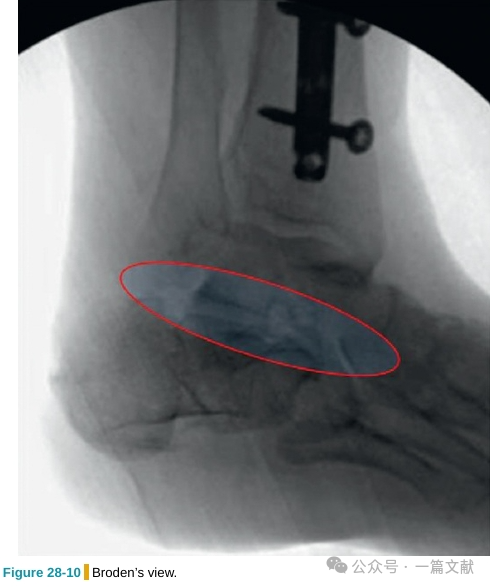

3.4 Broden’s位片:

通过拍摄不同倾斜角度的Broden’s位片,来综合评估后距关节面的受累情况。

患者侧卧位,踝关节保持在中立位置。X线以45度角透过距下关节,处于踝关节正位片和踝关节侧位片中间的角度。分别拍摄以头倾10度、20度、30度和40度的影像。这可评估大部分后距关节面的骨折线和骨折移位情况。头倾10度的影像显示后距关节面的后侧,而40度的影像显示关节面的前侧。20度和30度的影像则显示后距关节面的中部,最适于观察载距突情况。如下图: